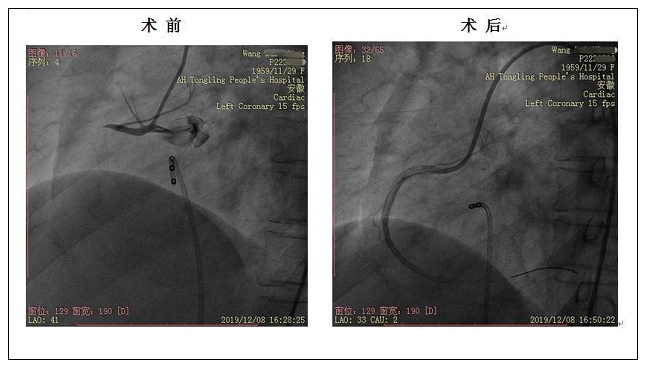

除颤仪监护、气管插管球囊辅助通气、大剂量血管活性药物快速滴注……容不得半点耽搁,只见数道白色身影快速转运着平车,车上承载着是生的希望。途中患者又发生室颤数次,多次电除颤终止发作同时送达导管室。此时,患者已命悬一线。汪坤主任带领的冠脉介入团队已准备就绪,深静脉置管、呼吸机辅助通气,植入临时起搏器保驾下行急诊冠脉造影+支架植入术,术中交感电风暴、恶性心律失常、心源性休克接踵而来,血压最低仅50/20mmHg。先后多次室颤不期而至,电除颤、胺碘酮应用、快速补液维持生命体征,患者心律逐渐归于平稳,血压上升至120/70mmHg上下。介入团队临危不乱、争分夺秒,凭借娴熟的技术、非凡的胆识、过硬的心理素质,一次次化险为夷,于右冠近段成功植入一枚支架,开通闭塞血管,挽救了患者生命。